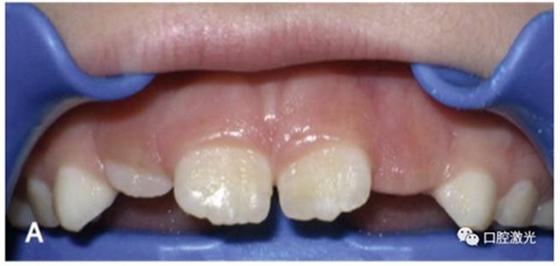

正常情況下,理想的托槽粘接位置為牙冠的中心位置。如果要達到這一目的,正畸牙醫(yī)首先需要能夠從視覺上觀察清楚牙冠的整體形態(tài)。如果存在牙齦覆蓋、遮擋的情況,就很難達到這一目的。這時,簡單的激光牙齦切割就可以很好的增加牙冠的暴露程度,達到更加準(zhǔn)確的粘接托槽的目的,從而也就加快了整個正畸療程的速度。通過下圖的病例可以看到,不僅患者節(jié)約了數(shù)月的等待時間,同時也創(chuàng)造了一個干凈的口腔環(huán)境,降低了在后續(xù)的正畸治療中可能導(dǎo)致牙齦增生的風(fēng)險。

治療前

激光牙齦切割后暴露更多的上前牙便于粘接托槽

當(dāng)天粘接托槽后即刻

4周后即可見明顯效果